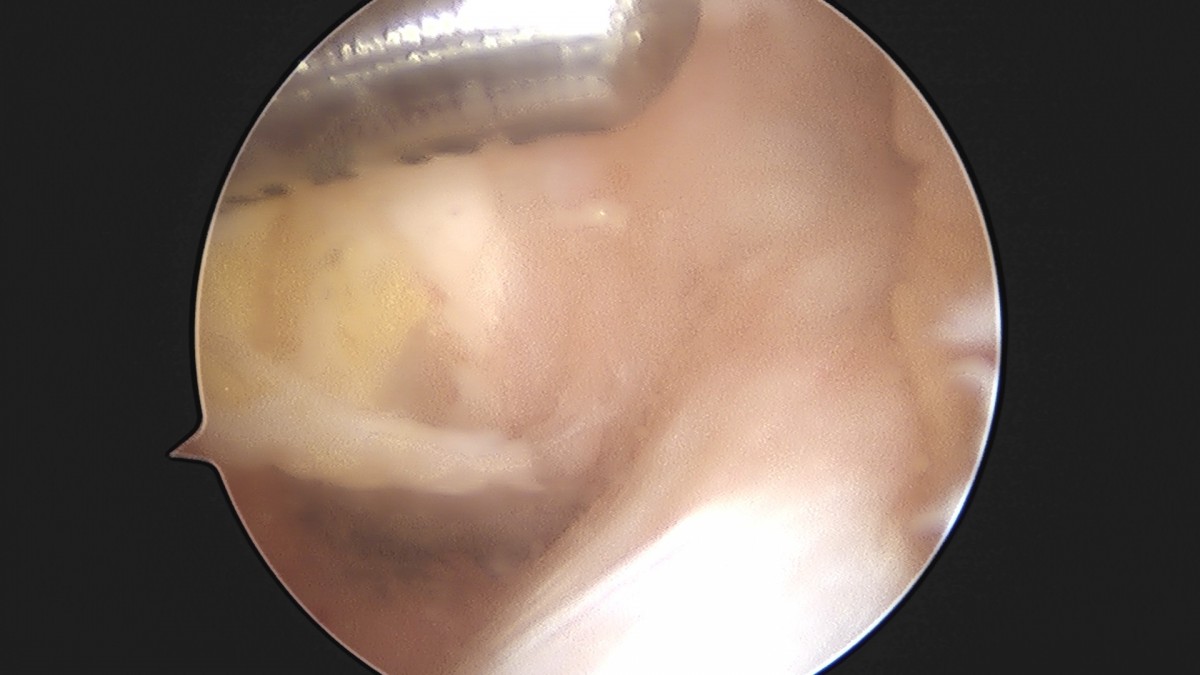

이재상원장님 무릎 반월상 연골판 절제술 박민O 환자

작성자 최고관리자 댓글 0건 조회 382회 작성일 25-09-16 15:46